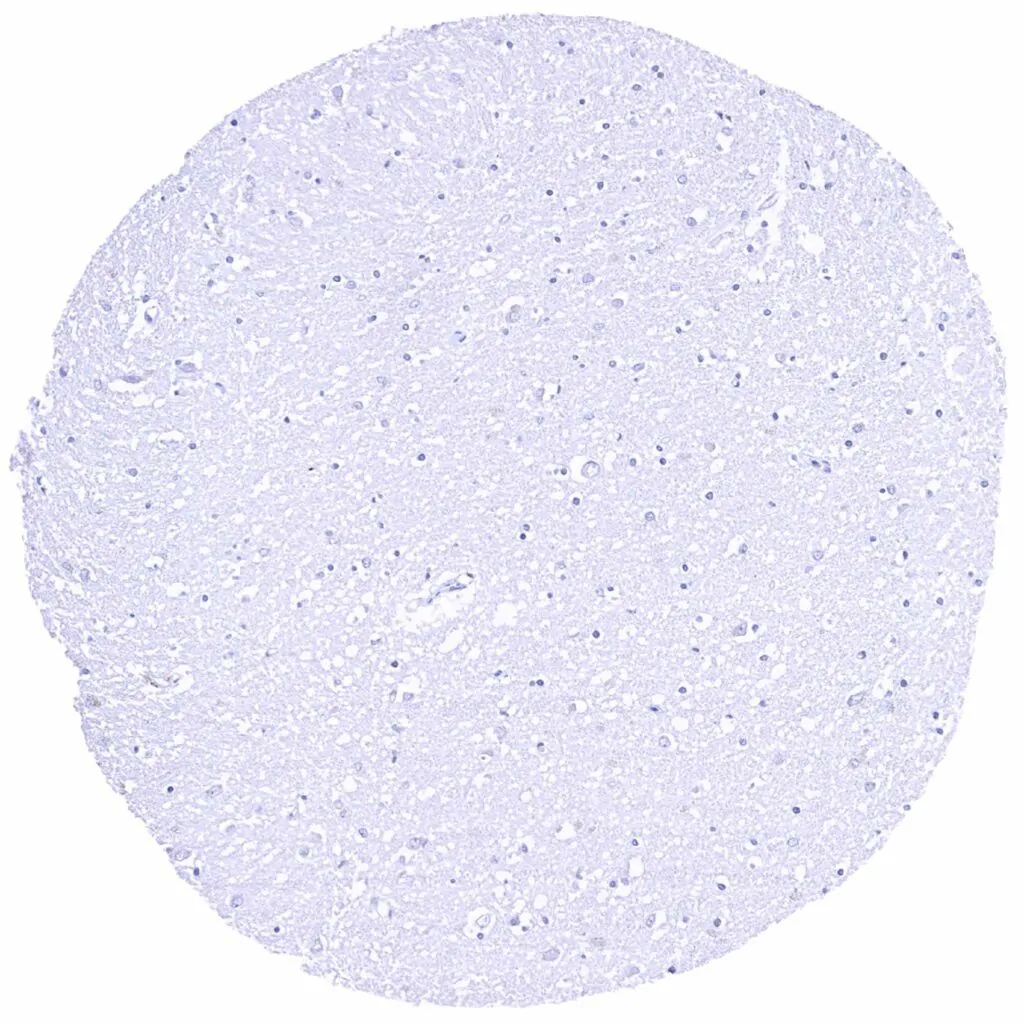

Cerebrum, grey matter